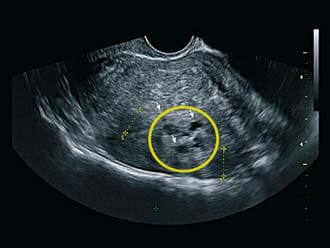

Миометрий диффузно неоднородный с гиперэхогенными включениями

В наши дни медицина даёт возможность определить появление диффузных изменений уже при ранних их появлениях, что значительно увеличивает возможности на успешное и быстрое излечение. Главным способом диагностики является УЗИ, на котором определяется нетипичная структура гомогенного миометрия.

Таким образом, диффузные изменения миометрия – это равномерно распределенные по всей мышечной толще неоднородности в структуре ткани, которые просматриваются при ультразвуковом обследовании и указывают на развитие аденомиоза.

Эхопризнаки диффузных изменений, регистрируемые при процедуре УЗИ – главный показатель неоднородности миометрия.

Термин обозначает способность ткани отражать ультразвуковые волны. При нормальном строении органа эхогенность низкая. Усиление эхогенности миометрия указывает на аденомиоз той или иной степени. Для аномальных зон характерны размытость контуров и неоднородность эхоструктуры миометрия.

При эндометриозе (аденомиозе) в мышечной толще фиксируют диффузные изменения структуры миометрия с гиперэхогенными включениями, то есть, с аномальными уплотнениями, имеющими очень высокую отражательную способность. Кроме того УЗИ показывает утолщение стенки матки до 40 – 50 мм за счет разрастания слизистого слоя.

Если обследование показывает несоответствие толщины эндометрия фазе менструального цикла, а структура миометрия диффузно изменена, это означает высокую вероятность патологии, степень которой зависит от выраженности эхопризнаков.

Проводится УЗИ и обнаруживаются характерные эхопризнаки, указывающие на диффузные изменения миометрия. Эхогенность (способность тканей различных органов отражать ультразвук) в норме бывает низкой. Миометрий выглядит однородным, изображение окрашено в серый цвет. На патологические изменения в толще стенки указывает появление на картине УЗИ светлых пятен и извилистых полос.

Толщина миометрия увеличивается за счет образования в его слоях железистых ячеек. Контуры на границе миометрия с эндометрием являются нечеткими. Увеличенная матка становится более округлой. Поверхность органа неровная, размытая.